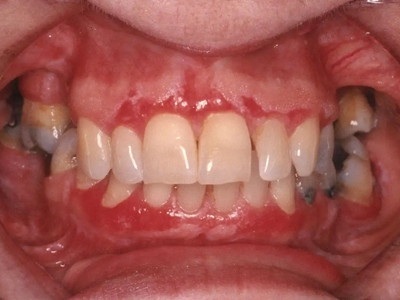

过敏性接触性口炎属Ⅳ型变态反应,是过敏体质者于局部接触某些物质后发生变态反应,而引发的一种炎症性疾病。发病前有用药史和过敏原的接触史,且与发病时间的潜伏期吻合,结合临床表现,一般可做出诊断。本病又称为接触性过敏性口炎,起病缓慢,损害位于接触处。

过敏性接触性口炎患者接触变应原后,经2-3天在接触部位发生病变,轻者黏膜肿胀发红,或形成红斑。重者发生水疱、糜烂或溃疡,甚至组织坏死。病变除在接触部位外,也可向邻近部位扩展。口腔科临床常见为修复材料引起的过敏性接触性口炎。

过敏性接触性口炎除了局部使用药物这一病因外,主要为充填和修复材料引起,如银汞合金、自凝塑料等。本病的发病多为Ⅳ型变态反应。